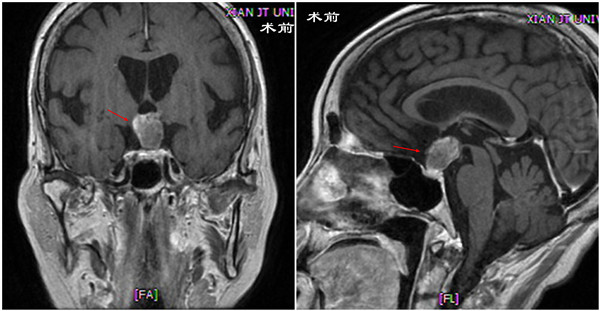

神经外科应用内镜技术经鼻切除颅咽管瘤

近日,神经外科应用内镜经鼻扩大颅底入路切除一例视交叉后型颅咽管瘤。 这是一名68岁的女性患者,以“视力下降2年,头痛、恶心、呕吐2月余”之主诉就诊于我院神经外科。患者近两年视力下降,2个多月前无明确原因出现头痛伴恶心、...